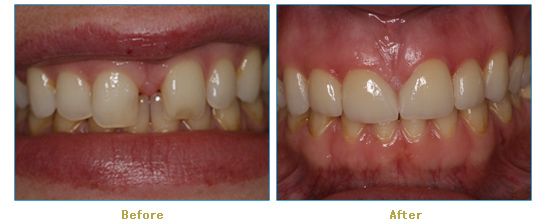

Dr. Cabianca has restored hundreds of smiles through the latest techniques in restorative and cosmetic dentistry. The following before and after photos document a few such cases in which Dr. Cabianca has replaced and reshaped teeth to produce wonderful smiles. Click on any of the images below to view larger versions of the photos.